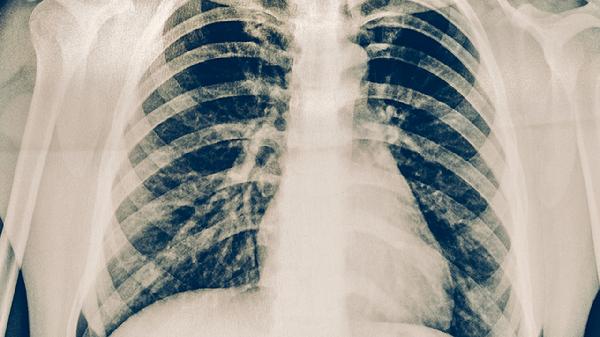

肋骨骨折患者应避免剧烈运动和突然转身,咳嗽时可用枕头轻压患处。饮食选择高蛋白食物如鱼肉、豆制品促进骨愈合,每日饮水1500-2000毫升稀释痰液。注意观察咳嗽是否伴有发热、脓痰等感染征象,出现呼吸困难、咯血等症状需急诊处理。康复期间定期复查X线观察骨折愈合情况。